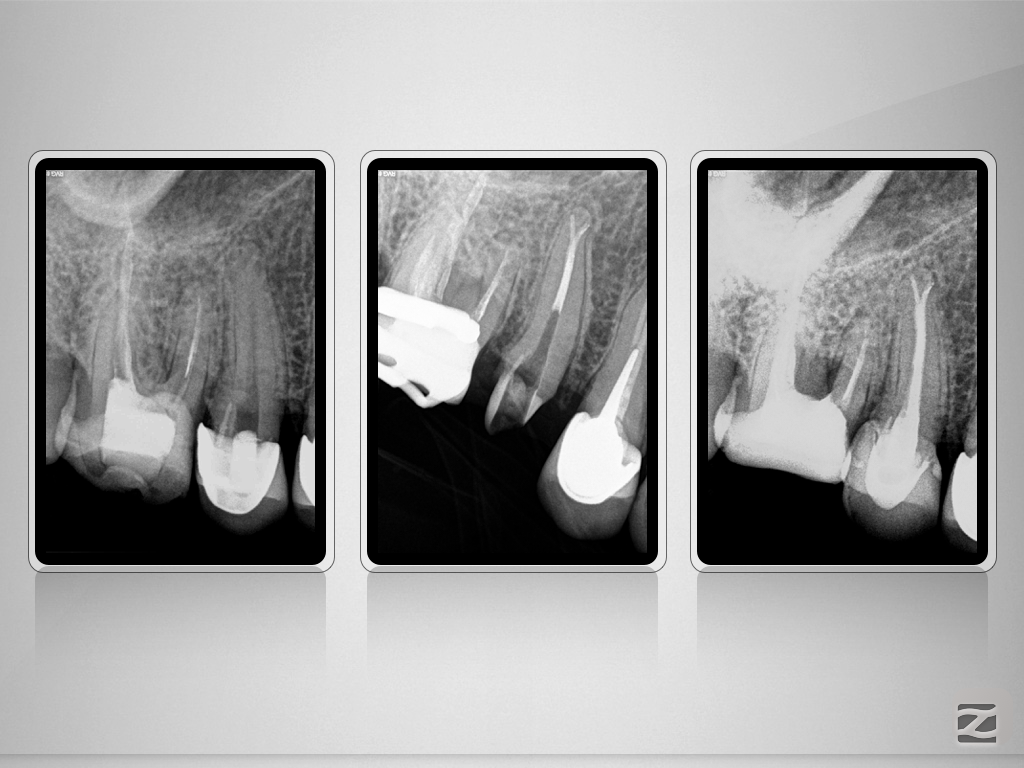

15D.009

Tiefe Aufgabelung